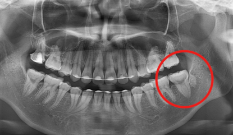

자료 채득

X-ray, 구강 내ㆍ외 카메라 사진, 치아 모형, 턱관절 및 치주 상태,